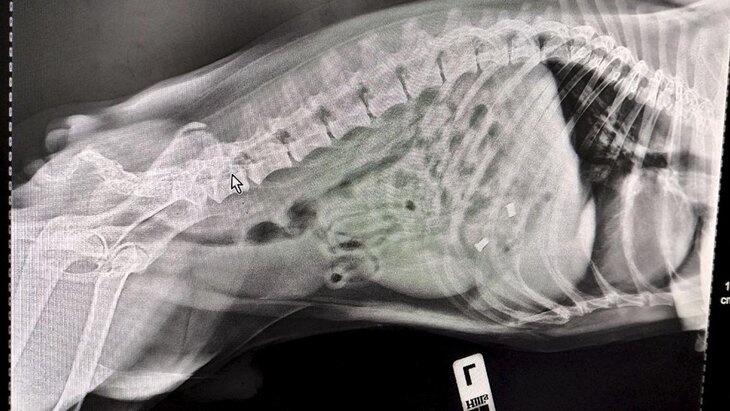

Фото: ГБУ "Мосветобъединение"

"Терапевт Алексей Щукин и УЗ-диагност Елена Сухарева провели УЗИ и рентген, установив, что внутри собаки находится больше чем один предмет. Поскольку Смайла доставили в ветклинику сразу же после происшествия, обошлось без операции. Специалисты вызвали медикаментозную рвоту и удалили предметы из желудка собаки", – отметили в пресс-службе.